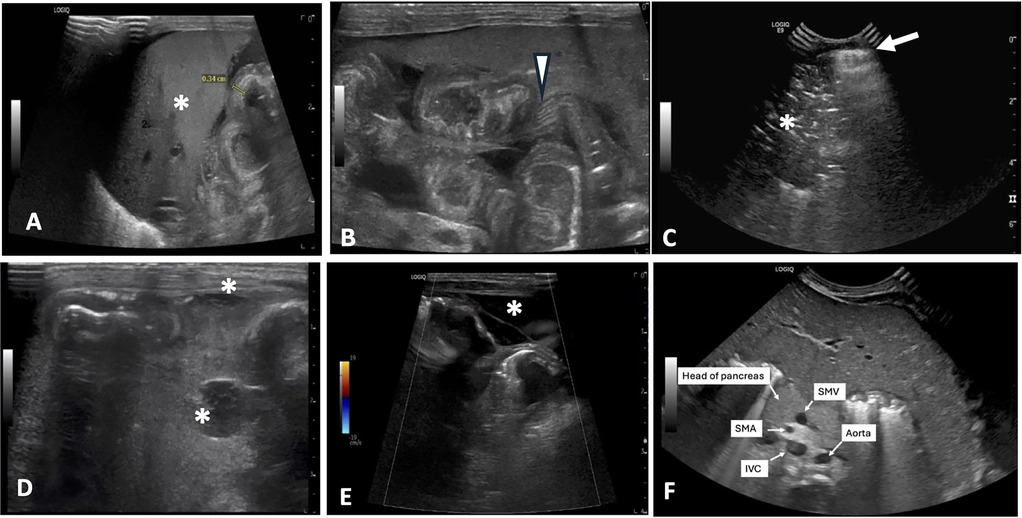

Representative AUS images of select HRF are shown in Figures 2A–F. The technical and clinical variables affecting the interpretability of each exam are summarized in Table 2. The interpretability of each AUS exam had a median number of HRF of 2 (IQR: 1–5), ranging from 0 to 8 HRF per exam. Six AUS exams from four neonates at the beginning of the study period lacked documentation on all eight HRFs; consequently, no positive HRFs were identified, despite all four neonates having confirmed bowel perforation on surgical pathology. The lack of documentation—whether due to missing details in the radiology report or absent in images —made it unclear whether the high-risk findings (HRF) were truly negative or simply not evaluated. After these initial AUS studies, our unit standardized AUS image acquisition and documentation, leading to gradual improvement in HRF documented, even the negative findings were reported.

Figure 2. Representative AUS images of select HRF. (A) Thickened, echogenic bowel measuring 0.34 cm near liver (*). (B) Echogenic bowel wall with thickening of bowel valvulae conniventes and their hypoechoic interspaces resembling zebra stripe pattern (arrowhead). (C) Pneumoperitoneum seen as a bright echogenic stripe with reverberation artifact (arrow) just above anterior aspect of liver. Portal venous gas is also present (*). (D) Complex fluid collections (*). (E) Segment of bowel with diminished perfusion as seen on color Doppler imaging. Free fluid with septation is also seen surrounding bowel (*). (F) Reversal of SMV/SMA orientation with the SMV positioned to the left of the SMA. AUS, abdominal ultrasound; HRF, high risk findings; SMV, superior mesenteric vein; SMA, superior mesenteric artery; IVC, inferior vena cava.